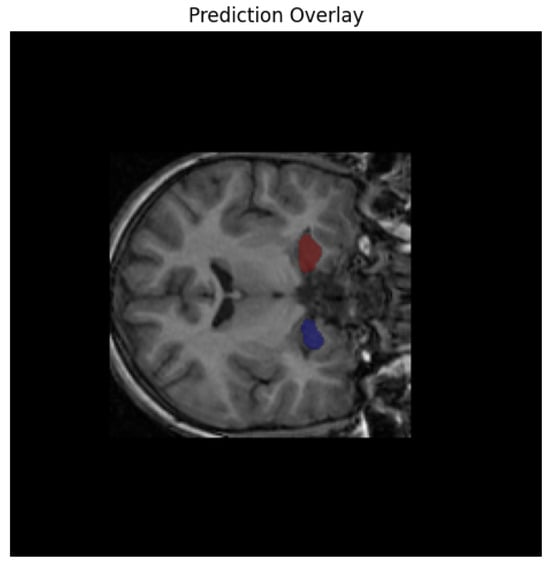

While quantitative metrics such as the Dice similarity coefficient provide essential numerical validation, the anatomical plausibility and spatial coherence of segmentation outputs must also be verified visually. To this end, overlay visualizations were generated by superimposing the predicted hippocampus masks onto the original T1-weighted MRI scans across axial, sagittal, and coronal planes. Figure 3 presents visual inspection confirmation that the model reliably captured the hippocampal contour, preserving the medial temporal morphology without significant over-segmentation or leakage into adjacent structures such as the amygdala or lateral ventricles [34]. These overlays also helped identify edge cases with partial coverage or morphological anomalies, enabling refined interpretation of volumetric outputs.

Figure 3.

Overlay visualization on axial, sagittal, and coronal planes.

Following segmentation, we conducted extensive post hoc analyses to identify individuals at risk of early neurodegeneration or accelerated brain aging. Using the derived hippocampal volumes, we flagged cases where the total volume fell below a conservative threshold of 5000 mm3 in subjects under the age of 16—an early atrophy marker. Additionally, the brain-age gap was computed as the difference between predicted biological brain age (derived from a regression model trained on hippocampal volume) and chronological age. A gap greater than 5 years was used to define accelerated aging. Subjects who met both criteria (low volume for age and high brain-age gap) were designated as high-risk. This criterion is supported by prior brain-age literature, where such deviations have been shown to correlate with cognitive decline and elevated risk of neurodegenerative progression [35]. While this threshold was originally validated in adult populations, its use here reflects a conservative and translational approach for detecting atypical neurodevelopment in younger cohorts as shown in Figure 4.

Figure 4.

Model’s predicted overlay results.